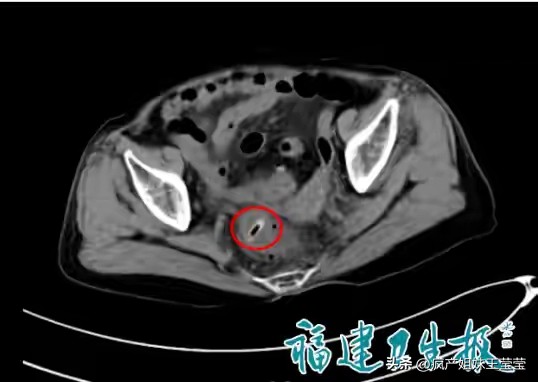

更让人揪心的是"隐形杀手"枣核。多位老人因吃红枣、八宝饭时误吞枣核,起初没有明显不适,直到腹痛难忍、发烧腹胀才就医。检查结果令人心惊:枣核两端尖锐,已刺穿肠壁,引发腹腔感染、腹膜炎,有的老人不得不切除部分坏死肠管,住进重症监护室。枣核体积小、吞咽无感觉,却能在短时间内造成肠穿孔,初期症状隐蔽,等剧痛出现时,往往已错过最佳救治时机。